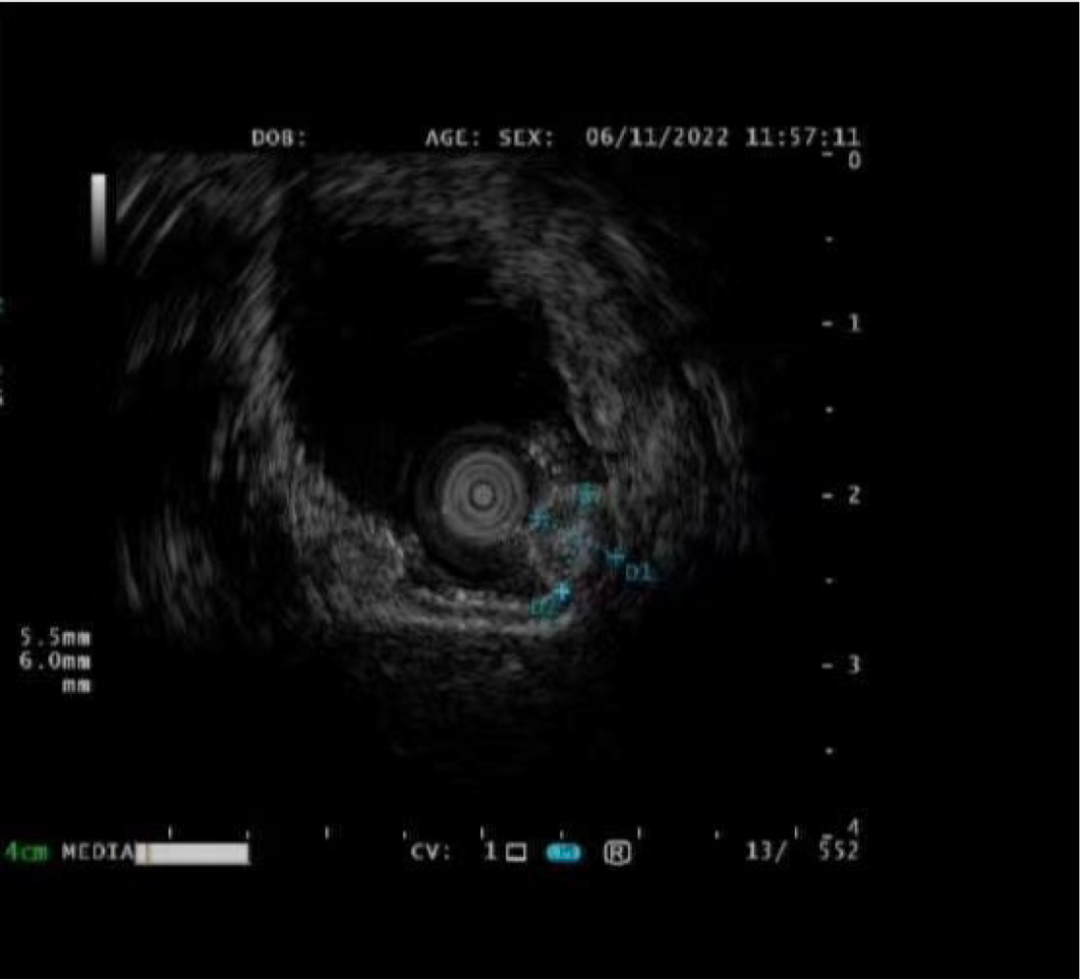

病例二:

赵某某,男,61岁,因“腹部不适伴大便次数增多2月余”入院,完善肠镜检查:直肠见一直径1.2cm 黏膜下隆起。超声内镜:直肠粘膜肌层低回声隆起,考虑神经内分泌肿瘤。

神经内分泌肿瘤有远处转移可能,与患者家属详细沟通、解释病情,完成充分的术前评估及准备后,孙院长实施黏膜下肿瘤挖除术,成功将病灶切除;术后病理诊断“神经内分泌肿瘤”,患者康复出院。